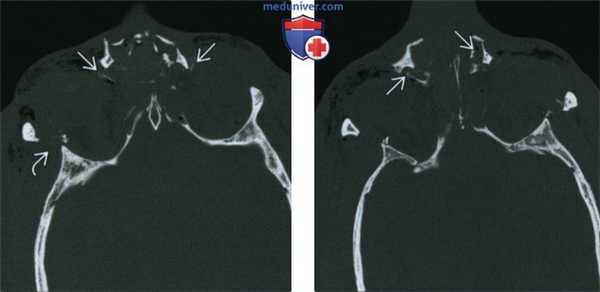

На аксиальных КТ-граммах признаками НОЭперелома являются: расхождение краев

назомаксиллярного шва, несимметричное

расположение носослезных каналов, затемнение и

разрушение решетчатых ячеек, депрессия и

смещение костей носа, перелом медиальной

стенки орбиты со смещением отломков, эмфизема

глазницы.

10. КТ-картина НОЭ-перелома:

КТ-картина

НОЭперелома:

а, б — телескопическое

смещение сломанных

костей носа назад, в

межорбитальное

пространство (стрелки).

в — прохождение линии

перелома через оба

носослезных канала

(длинные стрелки). г —

односторонний (геми-)

НОЭ-перелом

д — одностороннее расхождение назомаксиллярного шва на

аксиальной томограмме (длинная стрелка). Короткой стрелкой

отмечена зона диастаза скуловерхнечелюстного шва,

свидетельствующая о наличии у пострадавшего комбинации геми-НОЭи скулоорбитального переломов. е — аналогичное сочетание двух

переломов. Деструкция носослезного канала (длинная стрелка),

перелом скуловой дуги (короткая стрелка).